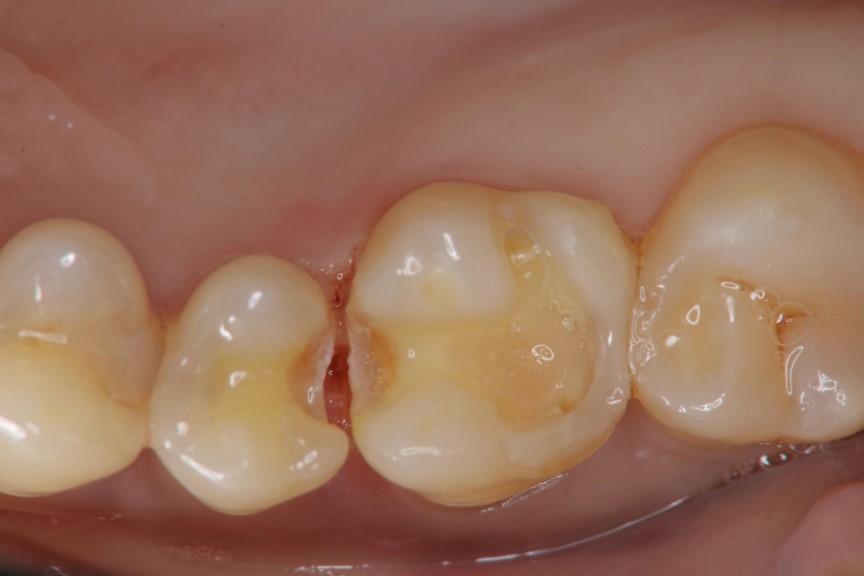

上橡皮障,隔水,黏著瓷塊

治療後,患者適應良好